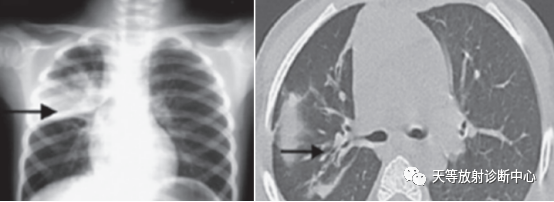

上图:重症肺炎支原体肺炎,右上肺实变影。CT显示病灶呈片状影及条索状影,支气管间质明显增厚,并轻度支气管扩张。